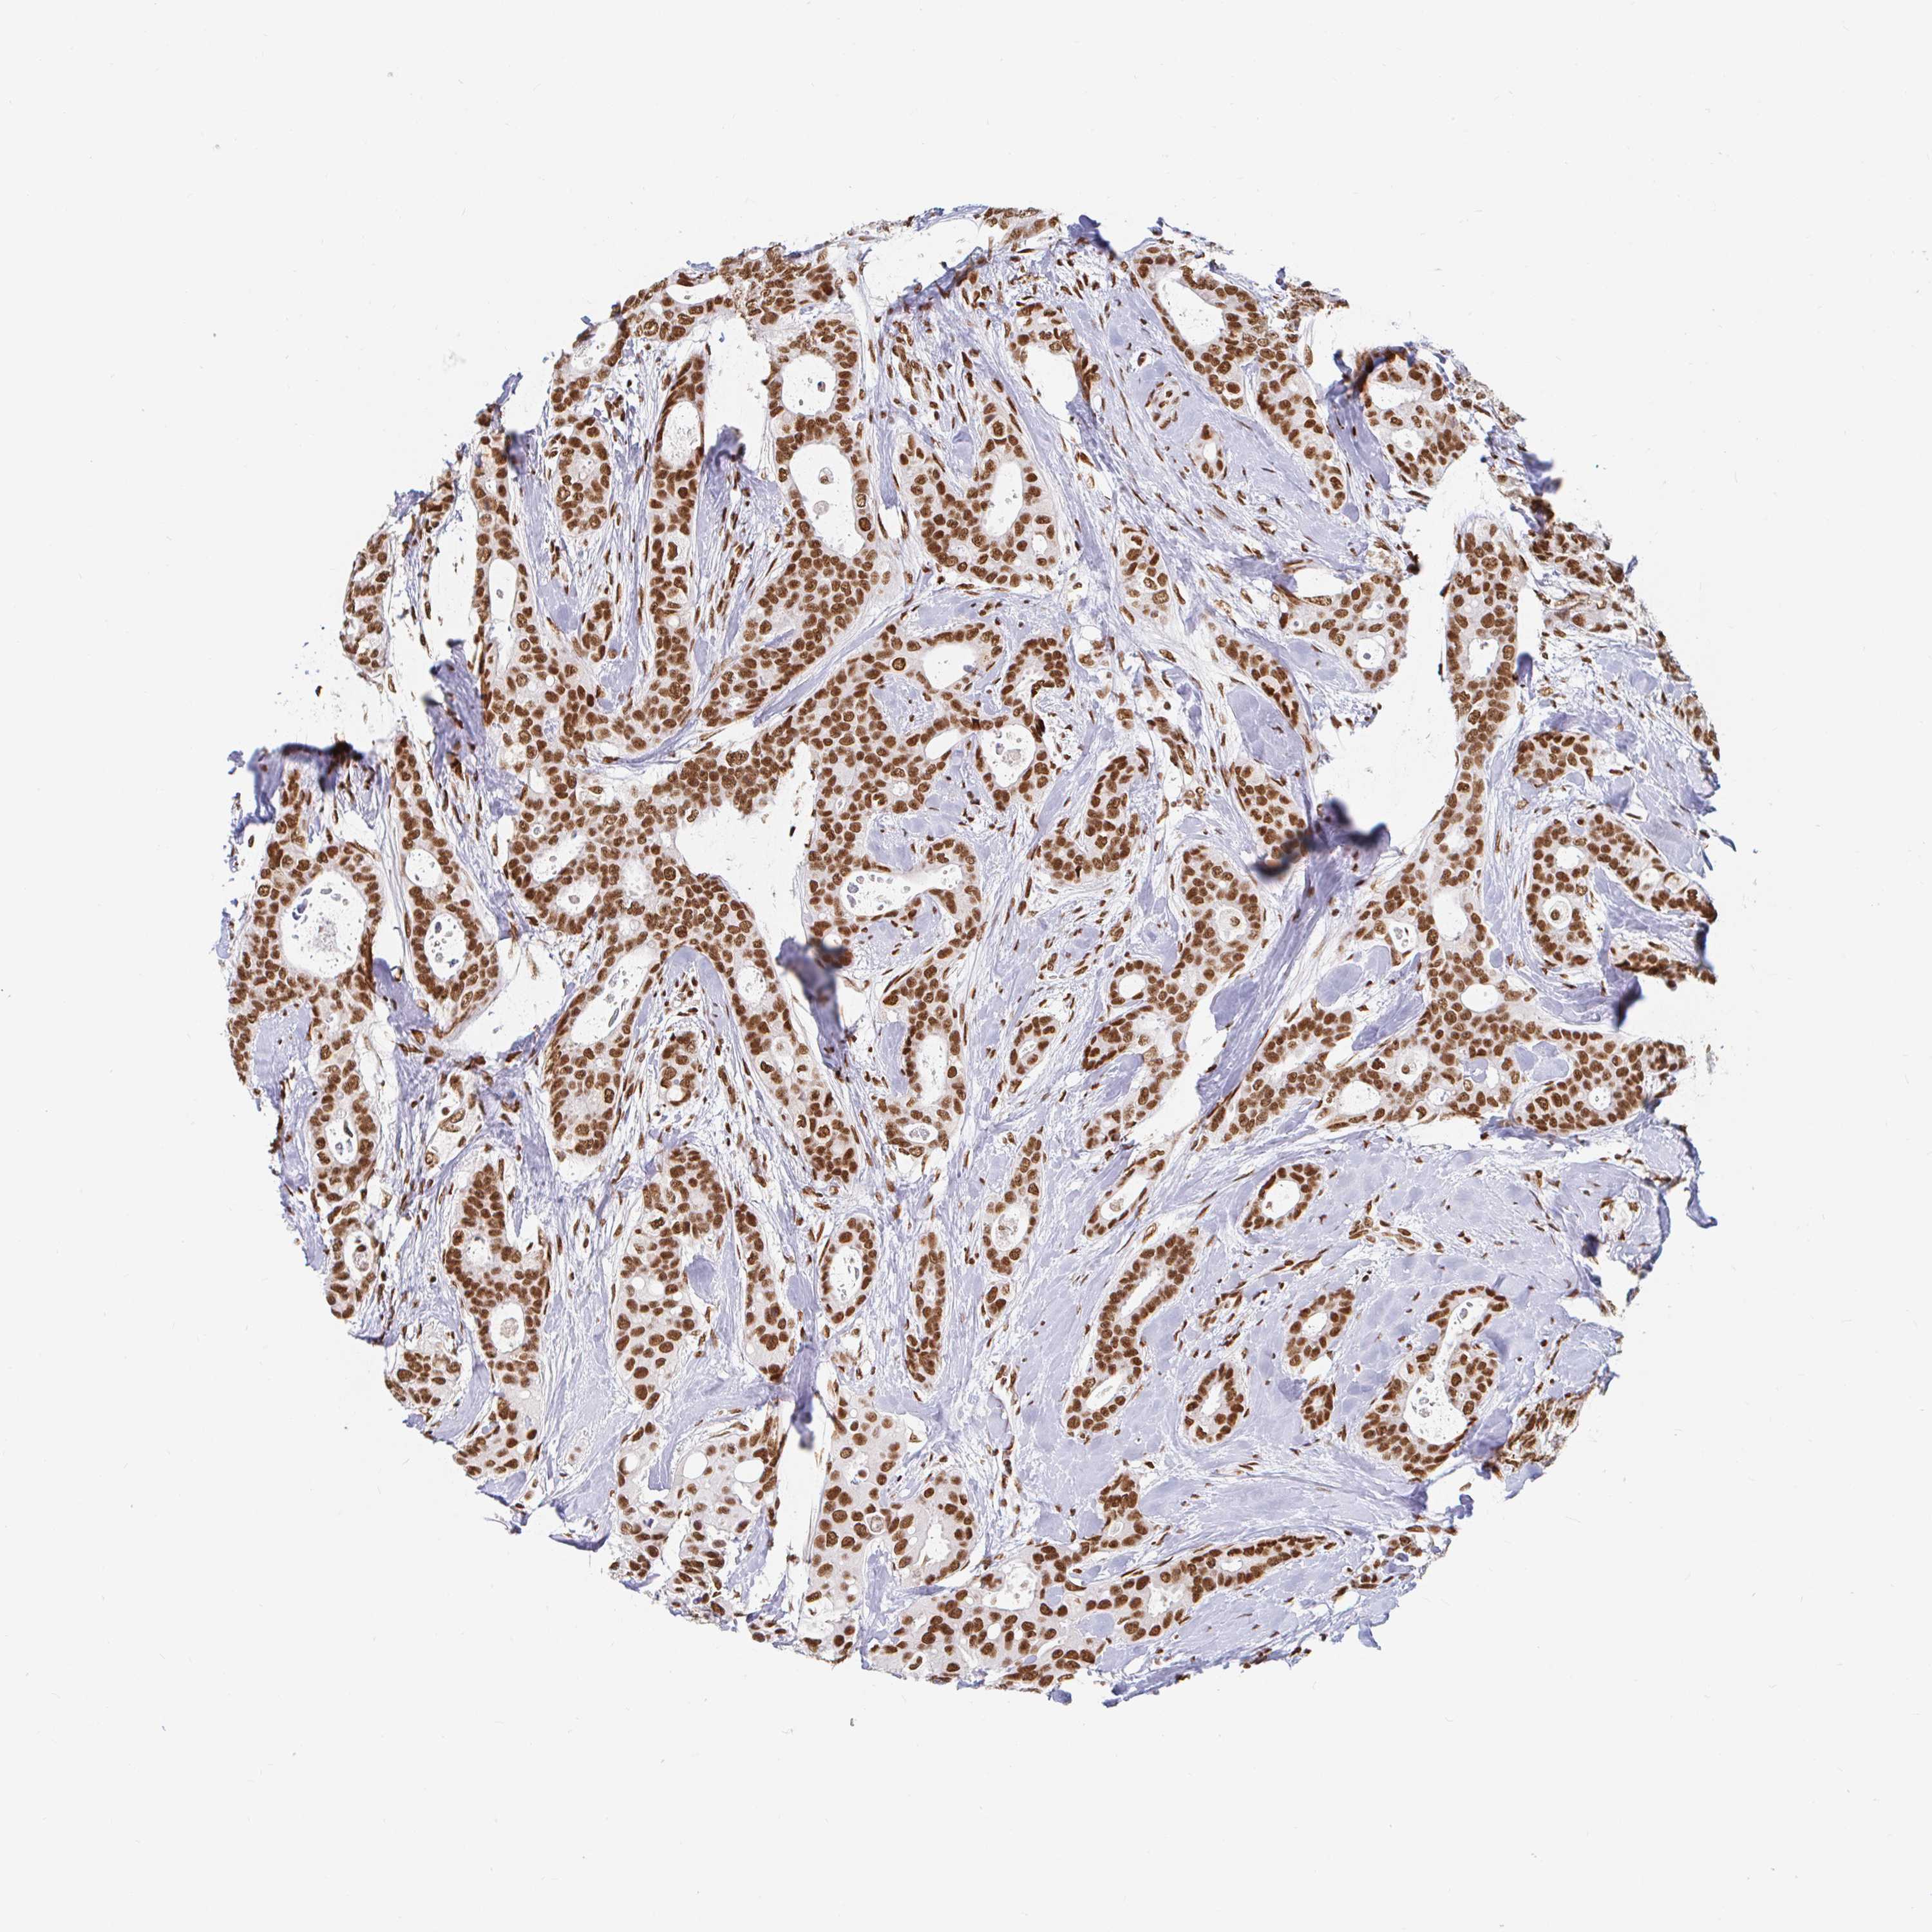

CANCER BREAST CANCER Show tissue menu

BRCA TCGA BRCA VALIDATION PROTEIN EXPRESSION

Breast cancer

Human cancer

Breast invasive carcinoma